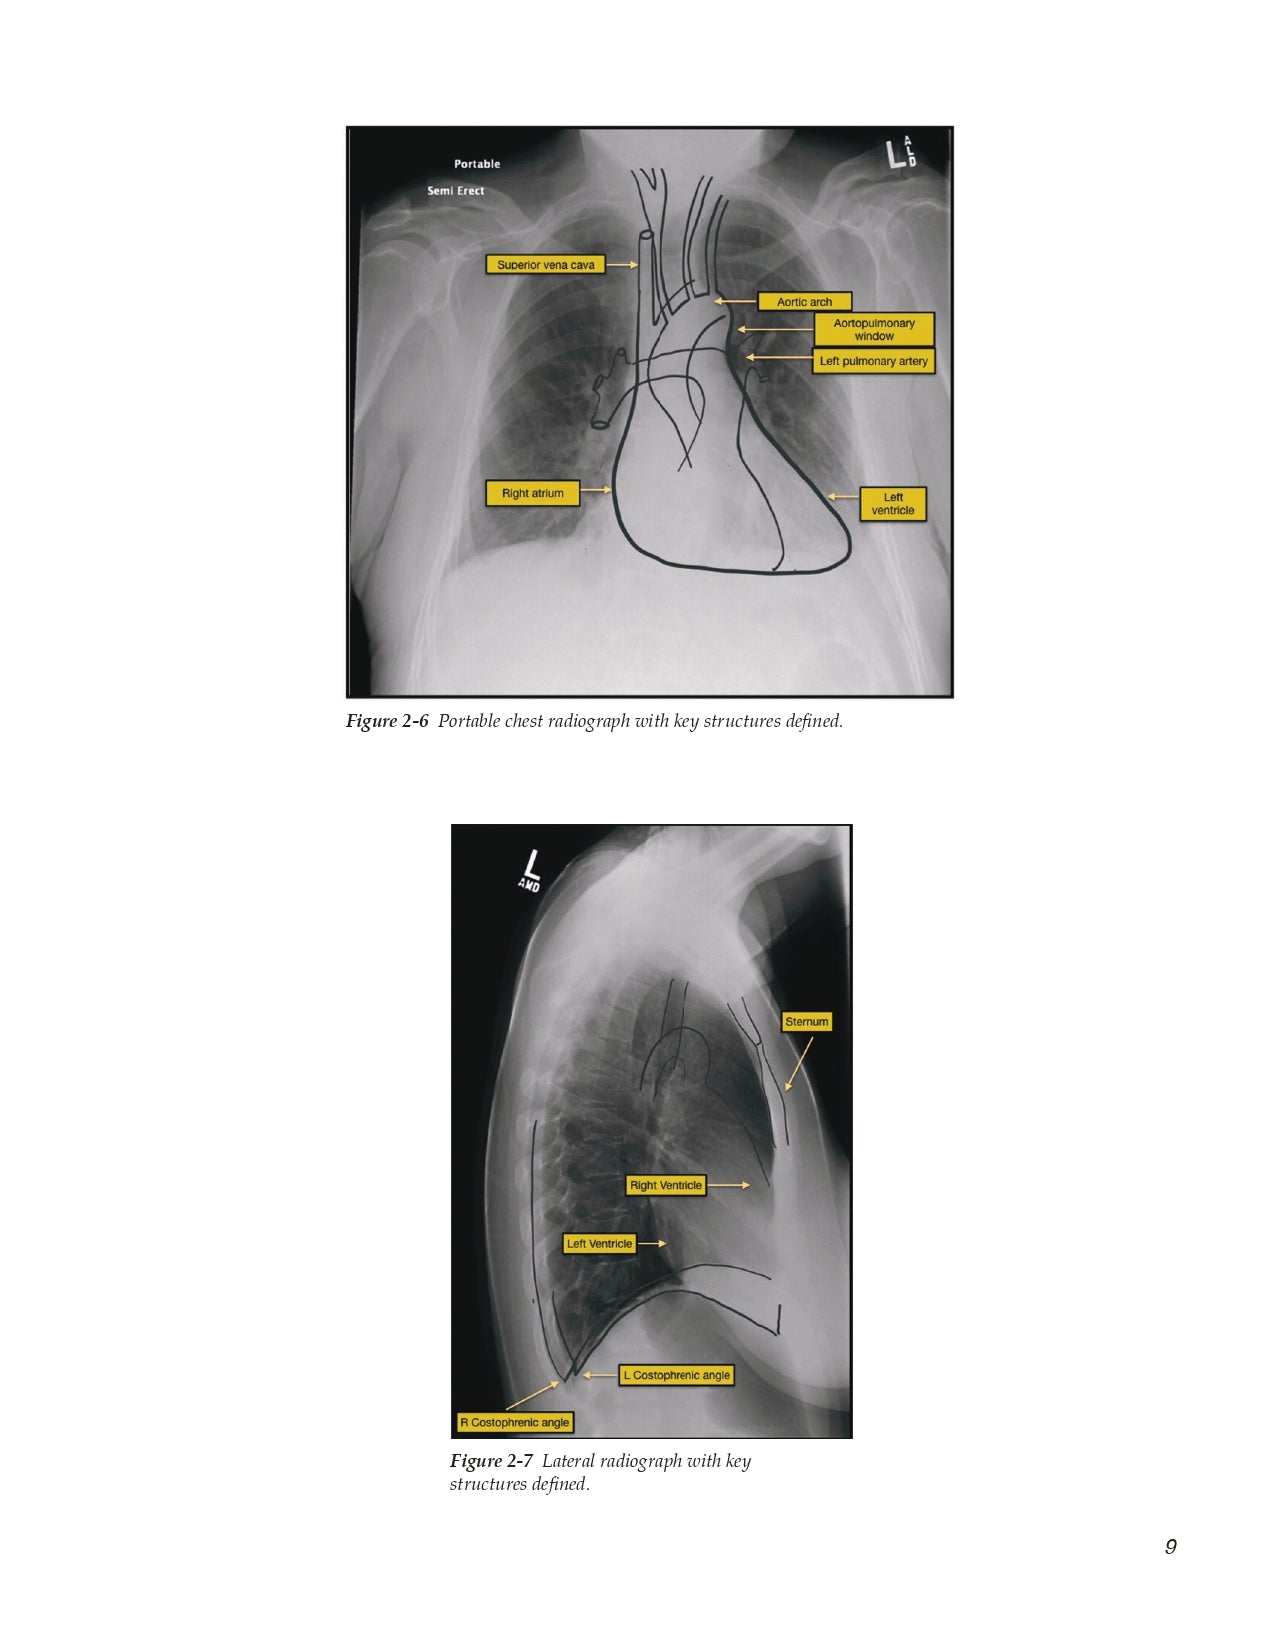

- Vessel Location for Catheter Placement